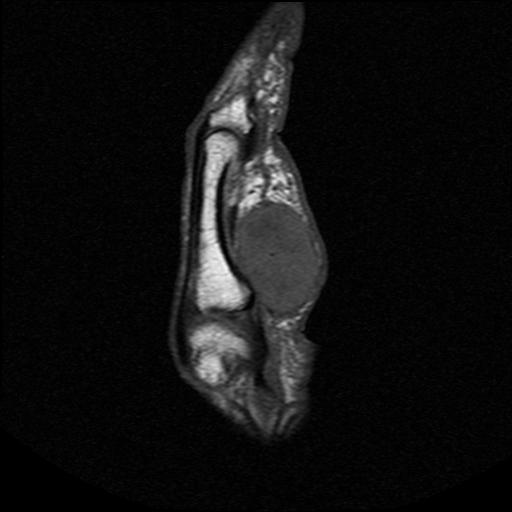

6. Synovial Chondromatosis

Diffuse swelling

May have calcification